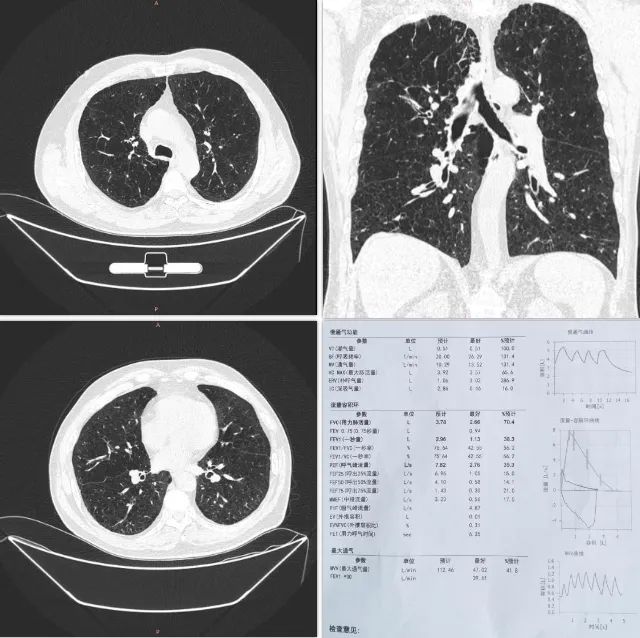

病案分析二

患者胸部CT和肺功能检查

患者男,64岁,以“反复咳嗽、咳痰、喘憋10余年,加重半月”为主诉住院。患者10年前无明显诱因出现咳嗽、咳痰,伴憋喘,对症治疗好转后停药。此后病情反复,常于秋冬季受凉后出现,每次持续2-3个月。曾在家先后应用氟替美维及布地格福三联吸入制剂,效果不佳。4个月前再次因上述症状加重,给予了第一次“热蒸汽消融术”治疗。术后患者明显感觉症状较之前减轻,经过术后恢复,为进一步治疗,考虑进行第二次“热蒸汽消融术”治疗。

经过充分的术前检查与讨论,该患者满足进行第二次“热蒸汽消融术”的适应症。